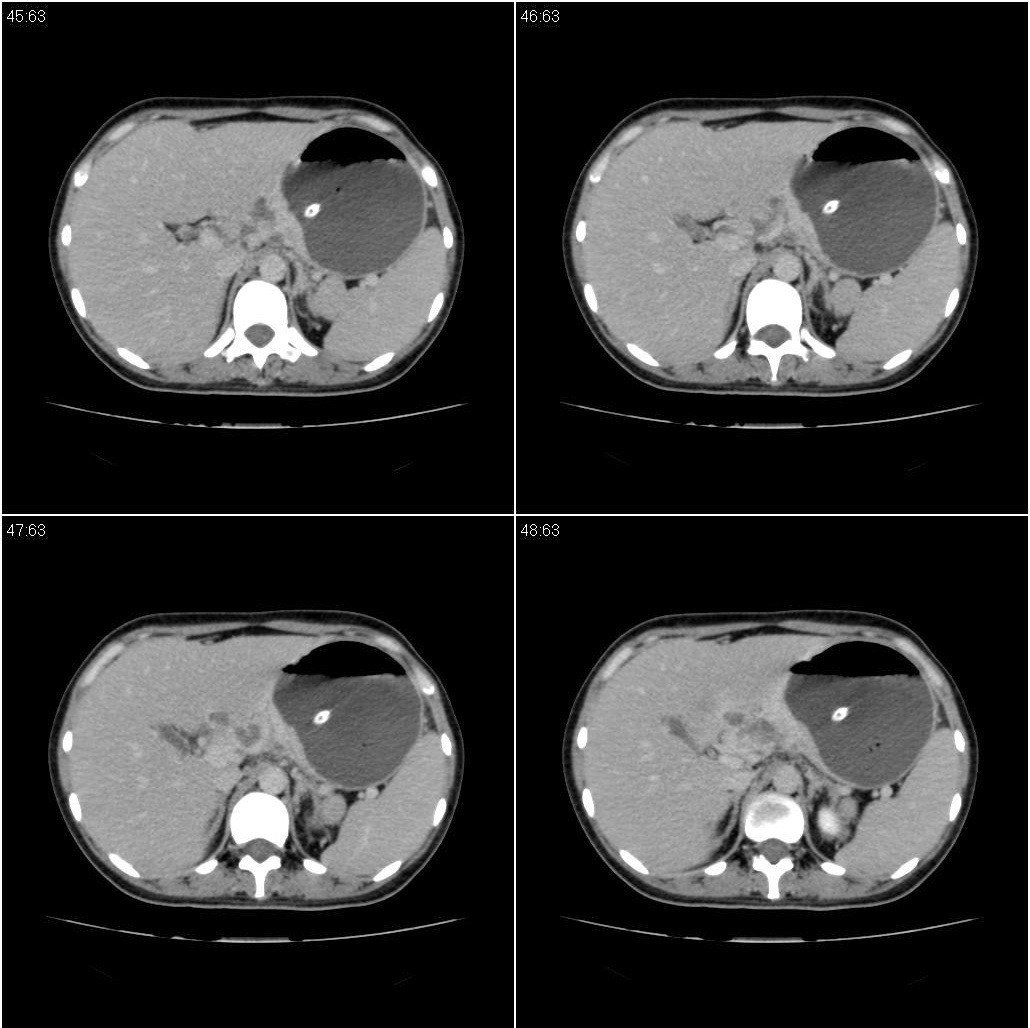

标题: CT21386:女性,33岁。4个月前因妊娠发现盆腔肿物。 [打印本页]

标题: CT21386:女性,33岁。4个月前因妊娠发现盆腔肿物。

女性,33岁。4个月前因妊娠发现盆腔肿物。ca-125: 1100

胃幽门部癌伴小弯侧和腹腔淋巴结转移,胃内有胃管。

胃窦贲门胃小弯好像都厚啊 ,胃窦处比较明显,而且胃腔扩张明显,考虑胃癌伴梗阻。

考虑胃癌伴腹腔内淋巴结转移。

胃壁局限性增厚,支持肿瘤性病变伴周围脓肿形成可能

未见明显肿大淋巴结,另肝脾大

支持;胃癌【浸润】幽门梗阻.胰头、胆囊及肝左叶受侵,副脾.

考虑胃窦占位并肝门部淋巴结转移

考虑胃窦部胃癌伴小弯侧和腹腔淋巴结转移。